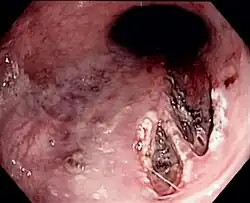

Zespół Mallory’ego-Weissa, obraz endoskopowy

Zespół Mallory’ego-Weissa stanowi przyczynę 5–15% przypadków krwawienia z górnego odcinka przewodu pokarmowego[25][26][27]. Krwawienie jest następstwem pęknięcia błony śluzowej i okazjonalnie podśluzowej przełyku w okolicy wpustu lub dolnej części przełyku w wyniku intensywnych wymiotów[27]. W wyniku silnego skurczu ściany jamy brzusznej przy jednoczesnym braku relaksacji wpustu dochodzi do znacznego wzrostu ciśnienia w przełyku, co powoduje pęknięcie jego błony śluzowej. Najczęściej występuje u alkoholików po intensywnym spożywaniu alkoholu, ale może również dotyczyć osób nienadużywających alkoholu o intensywnych wymiotach o innej przyczynie[25]. Klinicznie zwykle przebiega jako krwiste wymioty poprzedzone wymiotami bez śladu krwi[27].